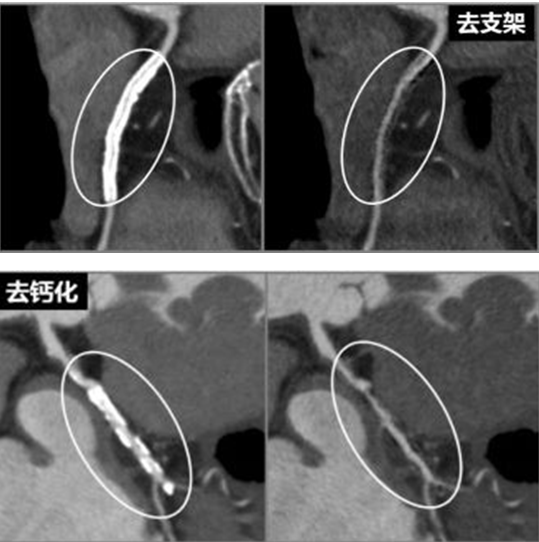

冠状动脉CT血管成像——冠脉CTA,因具有良好的时间和空间分辨率、安全无创、方便快捷以及三维成像等优势,成为临床上冠脉疾病的常规检查手段。但冠状动脉存在严重钙化斑块时,由于钙化斑块在扫描过程中产生的线束硬化伪影往往影响诊断医师的判断,从而高估了冠状动脉管腔的狭窄程度,导致出现假阳性,降低了冠状动脉CTA诊断的准确性。因此,克服钙化斑及金属伪影成为诊断和治疗冠状动脉疾病的必要条件。

据悉,佳能第五代Aquilion ONE开拓者AI-640 CT拥有极宽探测器仅用一圈就可以完成全心检查,覆盖范围最大、速度最快、图像最清晰,并且具备AMC智能运动伪影校正,可改善心脏跳动引起的运动伪影对图像的影响。另外,先进的门控去金属伪影技术,可以为装有心脏起搏器或支架术后患者的复查提供检查服务,帮助医生尽快做出精准的诊断,为患者争取救治时间,尤其适用于心脑血管疾病检查。